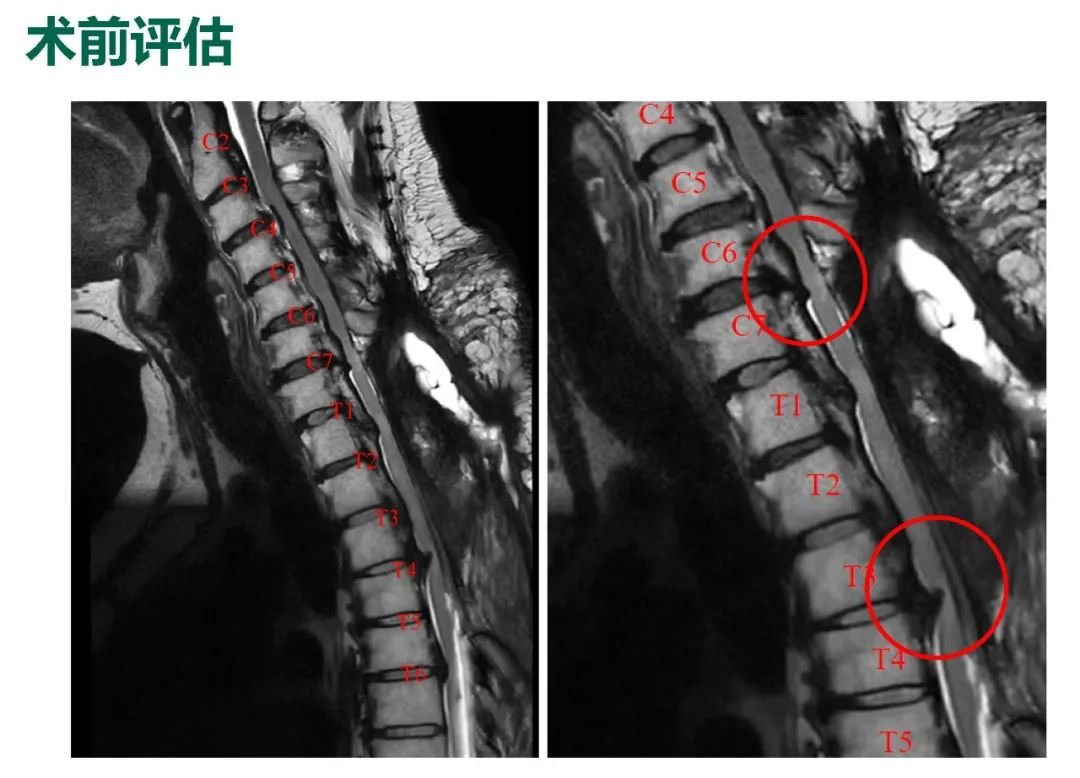

影像资料:

诊断&治疗:

Thoracic spinal stenosis(T2-T3)